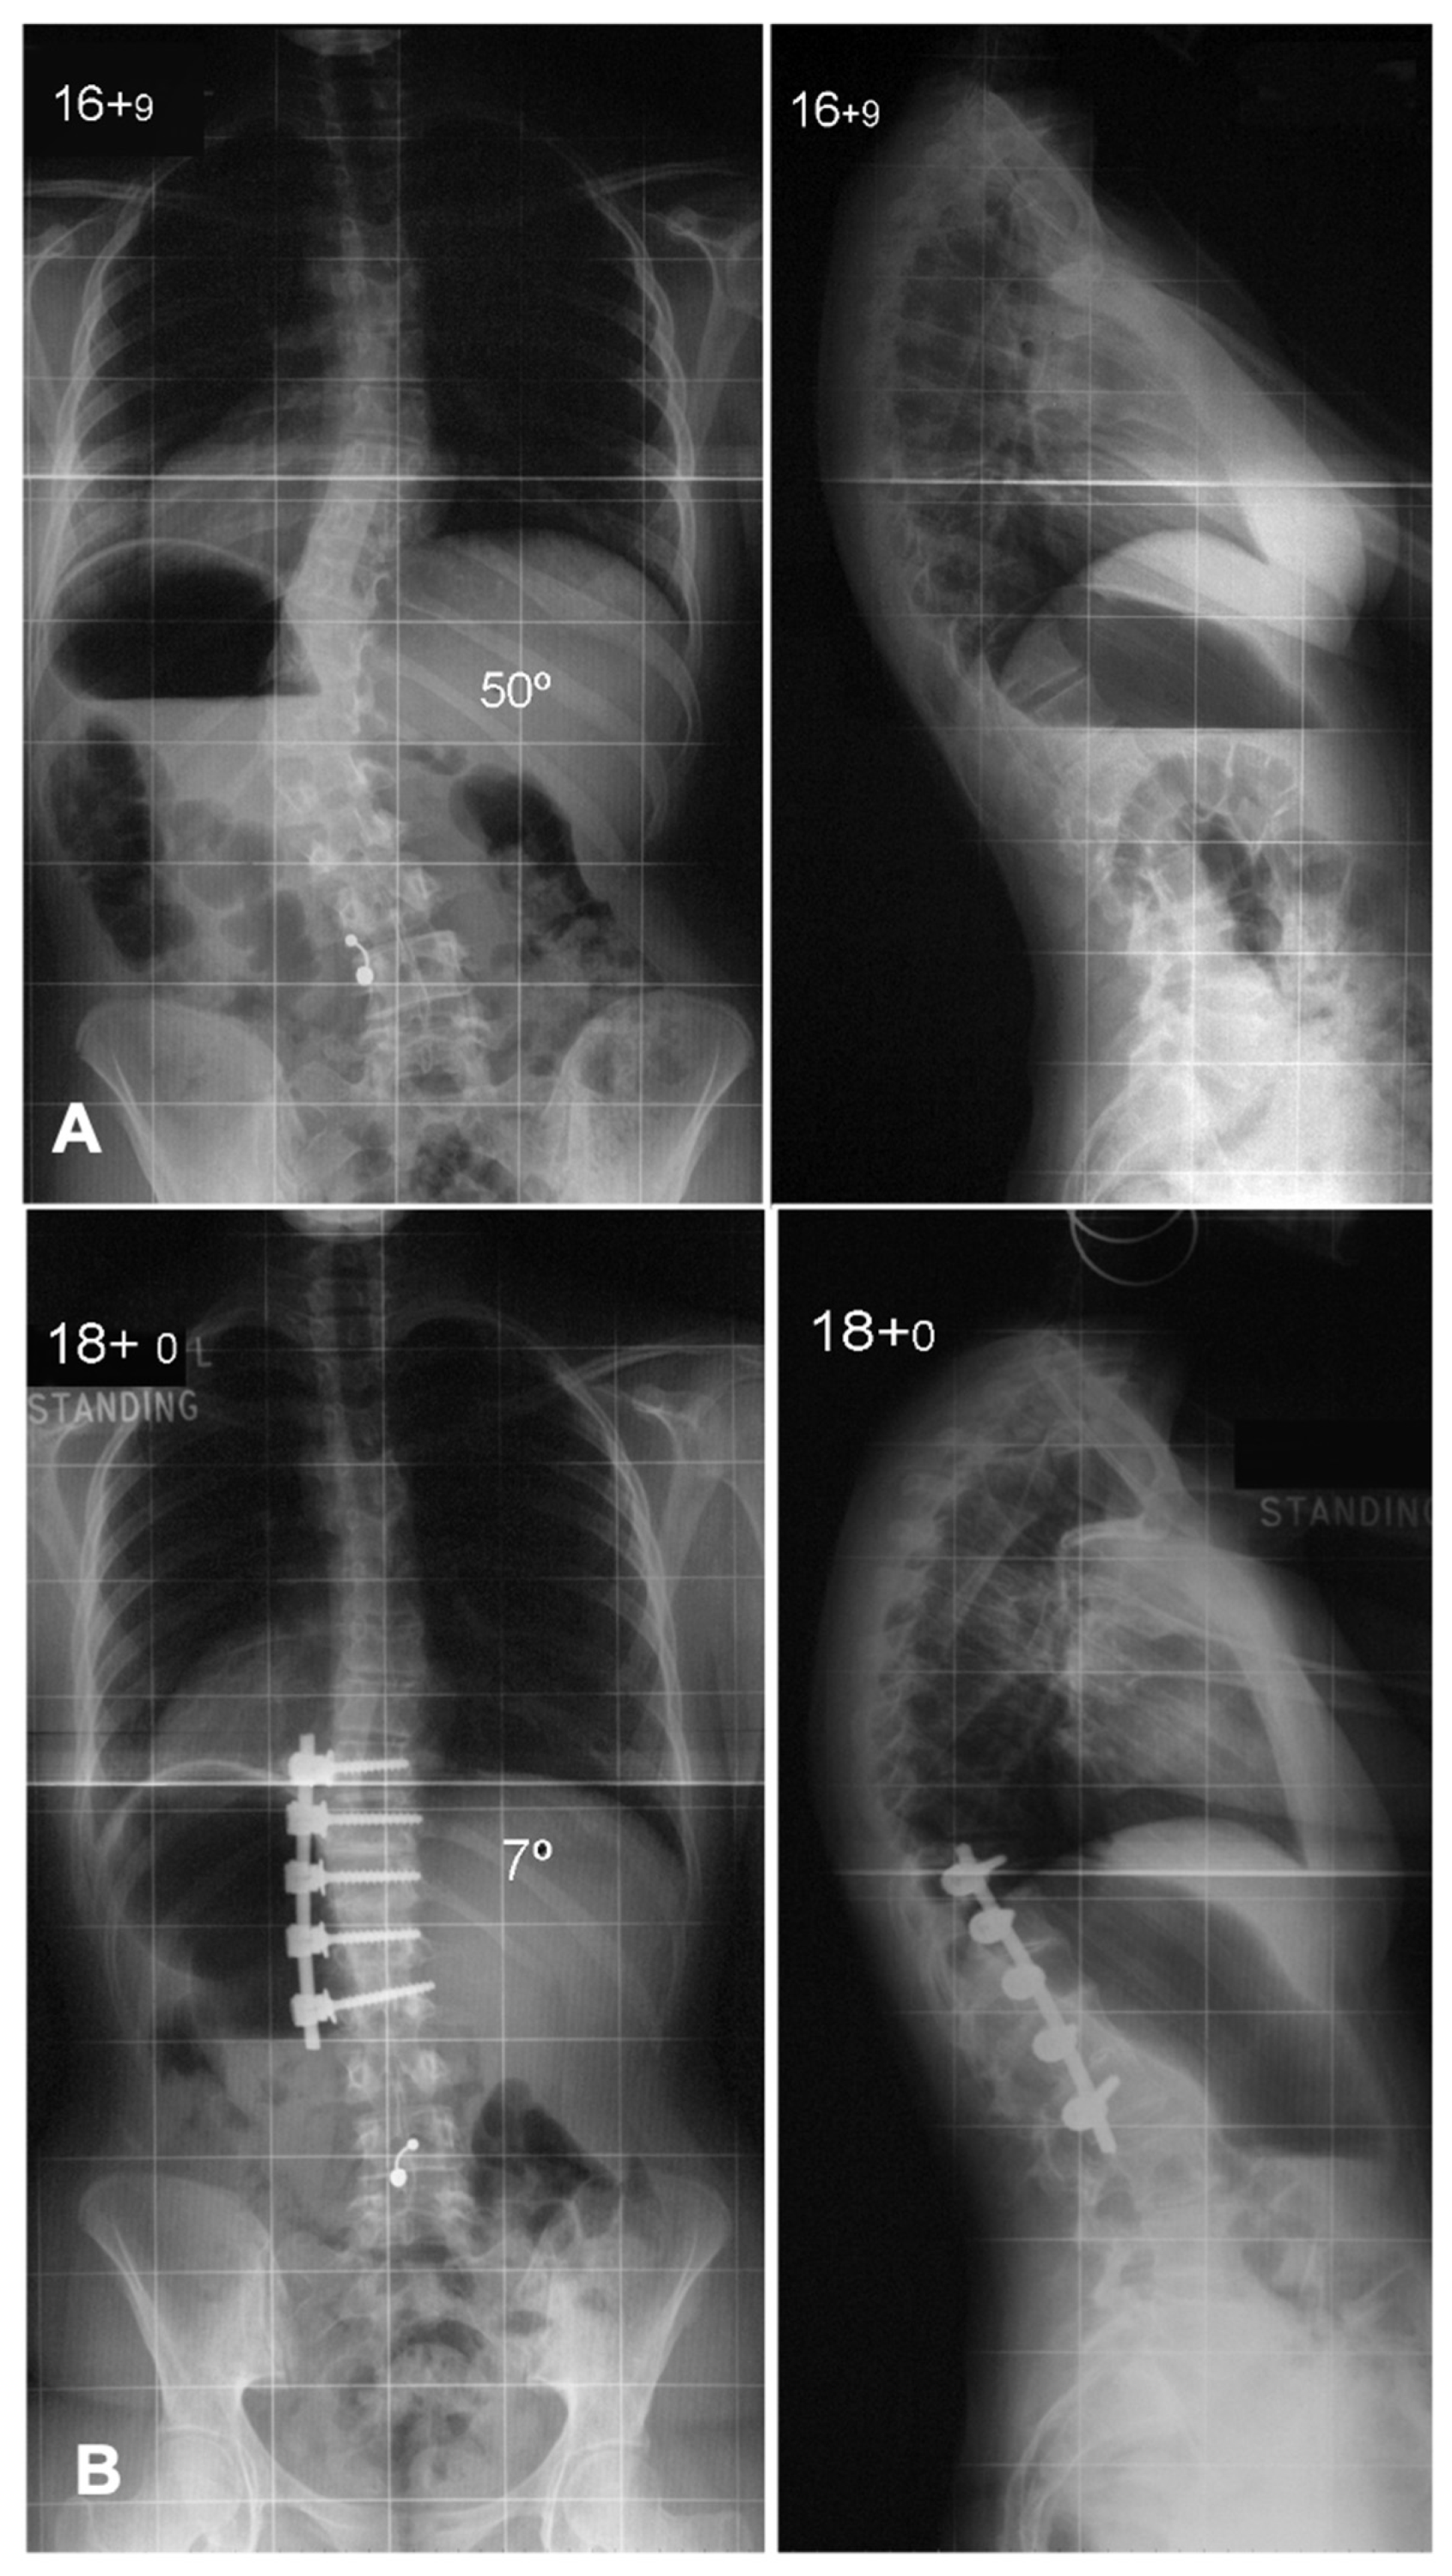

7. Anterior Versus Posterior Fusion in Lenke Type 5 Curves

Lenke 5 AIS, characterized by a primary thoracolumbar/lumbar [TL/L] curve with a compensatory thoracic curve, can be managed with either anterior spinal fusion [ASF] (Figure 6) or posterior spinal fusion [PSF] (Figure 7). The key argument favoring ASF is that it allows for shorter fusion constructs, potentially preserving an additional distal motion segment, which may reduce the risk of low back pain in later life if the fusion can be stopped at L3 rather than L4 [16]. Several studies have compared these approaches, showing that ASF achieves comparable coronal correction with fewer fused segments [17]. However, PSF, facilitated by modern segmental pedicle screw constructs, has become the standard approach due to its technical familiarity and ability to provide superior three-dimensional correction, particularly in terms of lumbar lordosis and thoracic kyphosis restoration [11,18]. Previous studies have indicated a greater loss of sagittal plane correction over time after ASF compared to PSF [17]. Additionally, PSF has been associated with better compensatory thoracic curve correction and improved trunk shift realignment [16,17]. Importantly, factors such as curve magnitude, lowest instrumented vertebra angle, and apical vertebra translation influence the decision on how far to extend the fusion distally. A predictive equation has been developed to guide this decision in PSF, helping to determine whether stopping at the Cobb-to-Cobb levels of the curve is sufficient or if additional distal levels should be included, in which case there may be an indication to consider performing an ASF instead [18]. Ultimately, both approaches have their strengths, and the choice should be individualized based on patient anatomy, surgical goals, and the surgeon’s expertise.